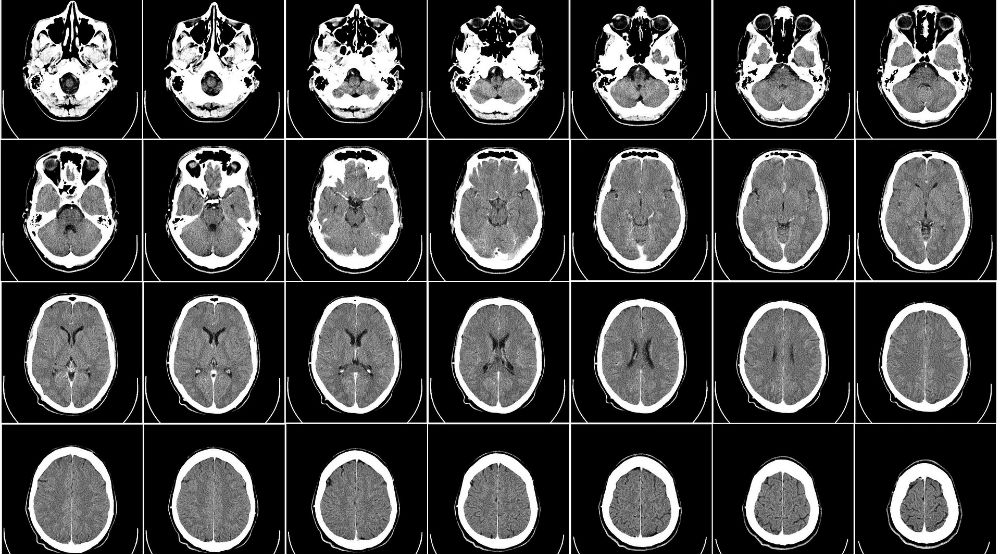

What is a traumatic brain injury?

A TBI is a brain injury caused by an external force hitting a person’s head. Car and truck crashes and accidents involving defective work equipment are leading causes of traumatic brain injuries. So too are falls; so elderly patients in hospitals or nursing home residents who receive negligent care are at particular risk for a traumatic brain injury.